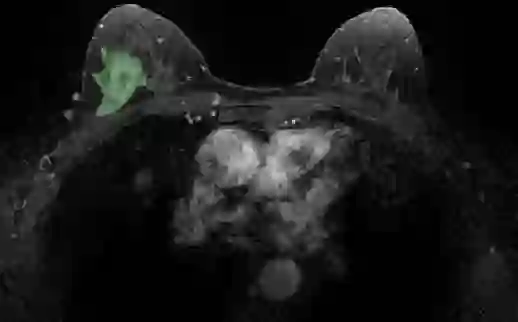

Most papers caution against using predictive models for disease stratification based on unselected radiomic features, as these features are affected by contouring variability. Instead, they advocate for the use of the Intraclass Correlation Coefficient (ICC) as a measure of stability for feature selection. However, the direct effect of segmentation variability on the predictive models is rarely studied. This study investigates the impact of segmentation variability on feature stability and predictive performance in radiomics-based prediction of Triple-Negative Breast Cancer (TNBC) subtype using Magnetic Resonance Imaging. A total of 244 images from the Duke dataset were used, with segmentation variability introduced through modifications of manual segmentations. For each mask, explainable radiomic features were selected using the Shapley Additive exPlanations method and used to train logistic regression models. Feature stability across segmentations was assessed via ICC, Pearson's correlation, and reliability scores quantifying the relationship between feature stability and segmentation variability. Results indicate that segmentation accuracy does not significantly impact predictive performance. While incorporating peritumoral information may reduce feature reproducibility, it does not diminish feature predictive capability. Moreover, feature selection in predictive models is not inherently tied to feature stability with respect to segmentation, suggesting that an overreliance on ICC or reliability scores for feature selection might exclude valuable predictive features.